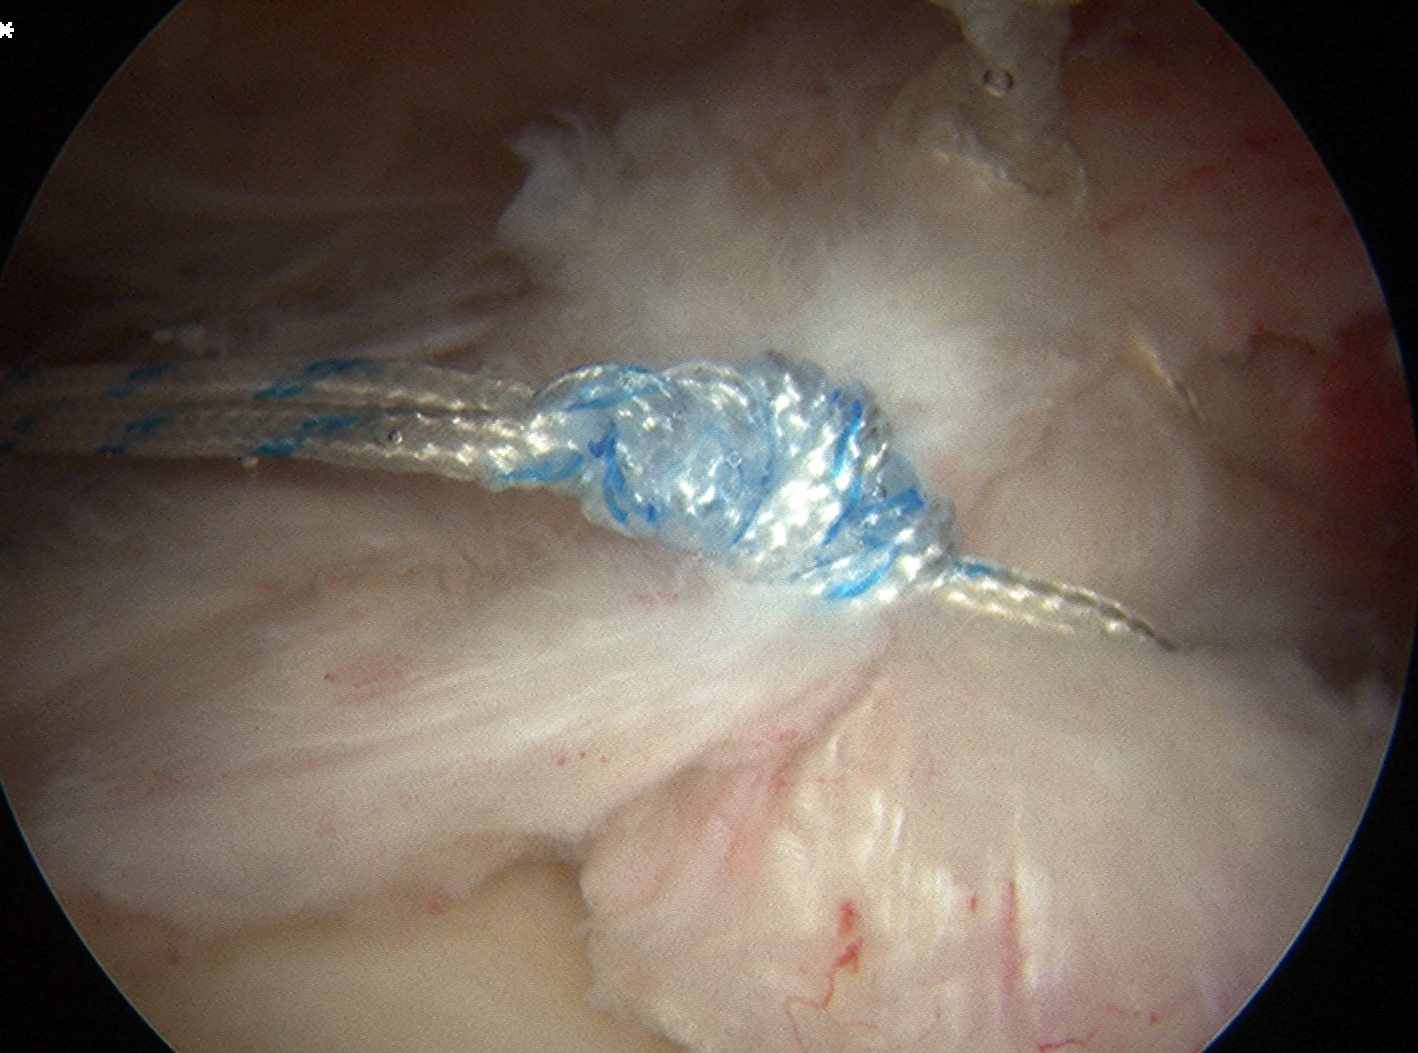

Tie sutures

- posterior to anterior / anterior to posterior

Double row

- either pass second lateral row of anchors or

- use foot print anchors, retrieve previous sutures

- can make suture bridge configuration